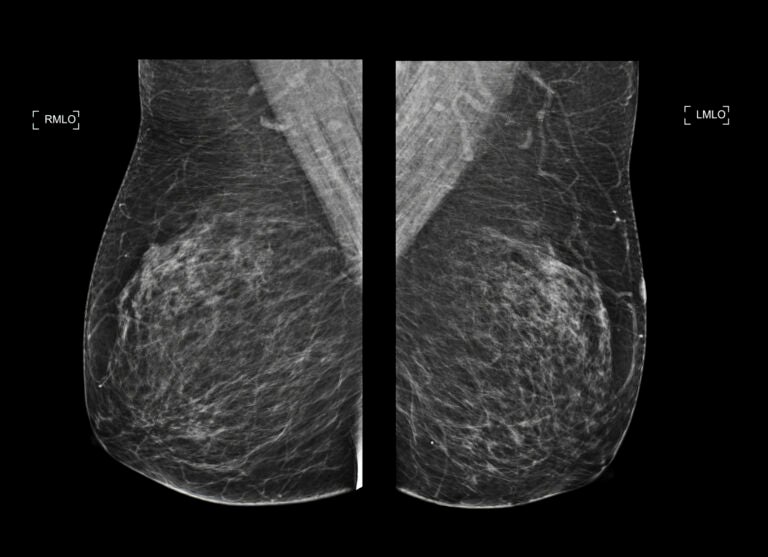

In a significant development, healthcare providers in Pennsylvania are now utilizing mammograms to detect early signs of heart disease in women. Traditionally used for breast cancer screening starting at age 40, these imaging tests are revealing important information about cardiovascular health by examining calcium buildup in the blood vessels of the breasts.

This calcium buildup, which appears as bright white lines or clusters on X-ray images, was previously thought to have no connection to heart disease. However, recent research indicates otherwise. According to Dr. Matthew Nudy, a noninvasive cardiologist and assistant professor at Penn State College of Medicine, the presence of these calcium deposits, known as breast arterial calcification (BAC), signals a higher risk of heart attack, stroke, or other cardiovascular complications as women age.

Many women over the age of 40 have undergone mammograms, which makes them a practical tool for assessing heart disease risk. As Dr. Nudy explains, while coronary artery calcium scans are typically used to assess cardiovascular risk, mammograms can provide similar insights with a larger patient population. “It’s already being done for breast cancer screening across large numbers of patients in the population,” he noted.

Radiologists now review each mammogram for signs of BAC and include this information in the reports sent to patients. This enables physicians to guide women toward specialists for further cardiovascular evaluations if necessary. Additionally, Jefferson Health, in collaboration with Solis Mammography, offers a program called Mammo+Heart. This service utilizes artificial intelligence to analyze BAC more comprehensively, although it comes at an additional cost for patients opting in.

While the absence of BAC does not eliminate heart disease risk, discovering it through mammograms provides an opportunity for early intervention. Experts recommend that women discuss these findings with their primary care providers and consider lifestyle changes or medications to mitigate their risk.